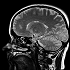

遷延性意識障害による植物状態と脳死の違いとは?

遷延性意識障害は、大脳が大規模な損傷を受けていても脳幹は活動して自発呼吸を維持して生存しているが、脳死は脳幹が活動を停止し、いずれ死に至る。

医学的にみる遷延性意識障害の原因とは

医学的な遷延性意識障害の原因は様々あるが、主な原因は脳の細胞が何らかのダメージ受けて死滅・破壊されることである。

遷延性意識障害とは?

遷延性意識障害は、主に知覚や意識を司る大脳が交通事故などにより損傷することでこん睡状態となった状態を指す。